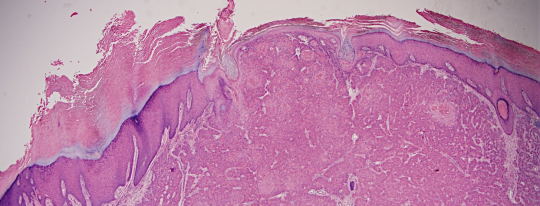

VA9: Left Forearm, Squamous Cell Carcinoma, Invasive

VA9: Left Forearm, Adjacent Normal